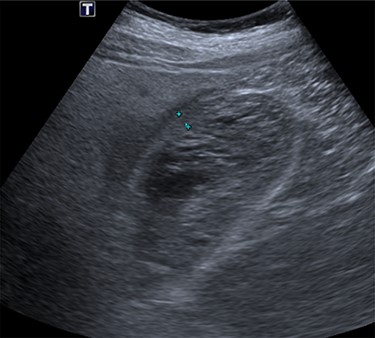

The emergency physicians arranged an urgent non-contrast computerized tomography (CT) scan of the abdomen and pelvis. This revealed hyperdense nodular soft tissue filling the gallbladder lumen with a non-thickened but prominent gallbladder wall, as shown in Fig. 1. There was biliary dilatation, with extensive fat stranding and fluid surrounding the gallbladder neck, porta hepatic region and common bile duct. The reporting radiologist’s differentials included malignancy or haemorrhagic cholecystitis, and magnetic resonance imaging (MRI) was advised.

Coronal non-contrast CT of abdomen on day of presentation, showing hyperdense nodular soft tissue filling the gallbladder lumen.